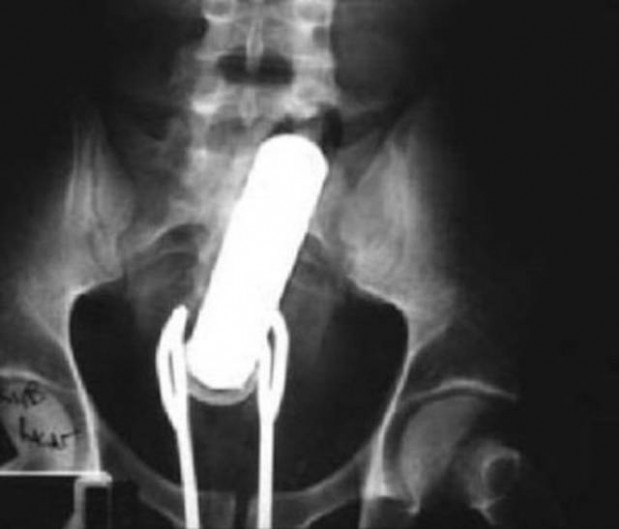

#10 Miehen jumissa oleva seksilelu ja pihdit, joilla hän yritti saada sen pois